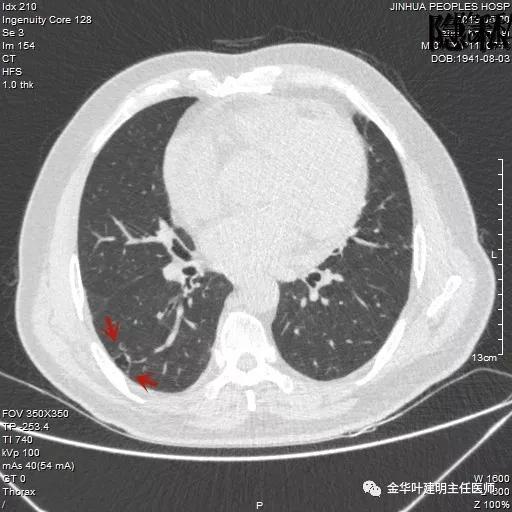

以上是2018年5月的片子,此处也呈空腔性病灶,但也点像是个肺大泡,因为绿色箭头所指处也有肺大泡。